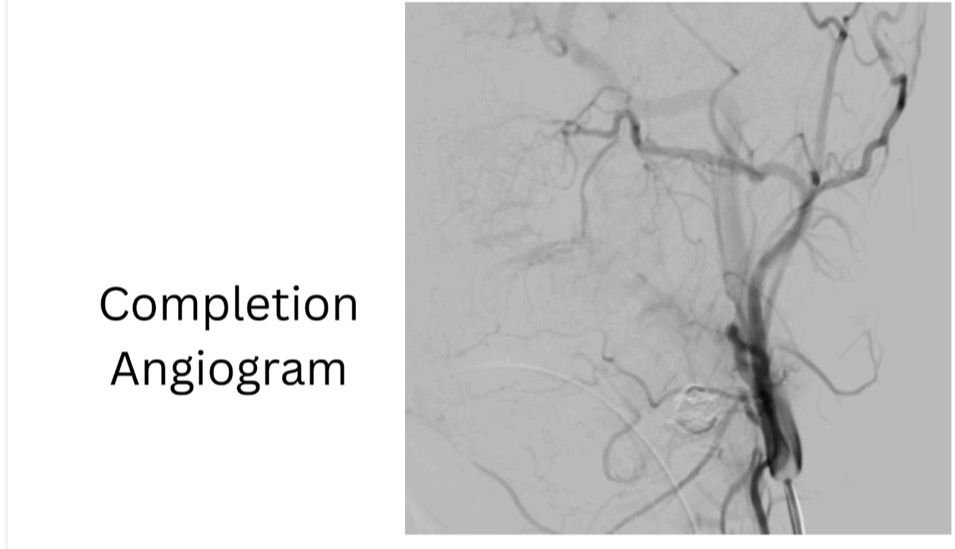

ومن جانبه، ذكر الدكتور احمد كمال المدير التنفيذي للمستشفيات الجامعية، أنه تم تجهيز وحدة القسطرة على الفور، حيث نجح الفريق الطبي في غلق التمدد الشرياني باستخدام حلزونات دقيقة عبر القسطرة التداخلية، مما أسهم في السيطرة الكاملة على النزيف دون الحاجة إلى جراحة تقليدية، وتقليل احتمالات المضاعفات.

وأكد الدكتور محمد زاكي رئيس قسم الأشعة، بأن الحالة خرجت في وعي كامل مع استقرار تام في العلامات الحيوية، مؤكدًا أن هذا التدخل يمثل نموذجًا للتنسيق السريع بين الفرق الطبية في الحالات الطارئة.